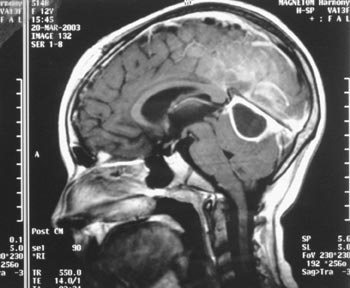

Εικόνα 5. ΜRI (3o 24ωρο):

υποσκληρίδια συλλογή πύου μεταξύ παρεγκεφαλίδας και σκηνιδίου.